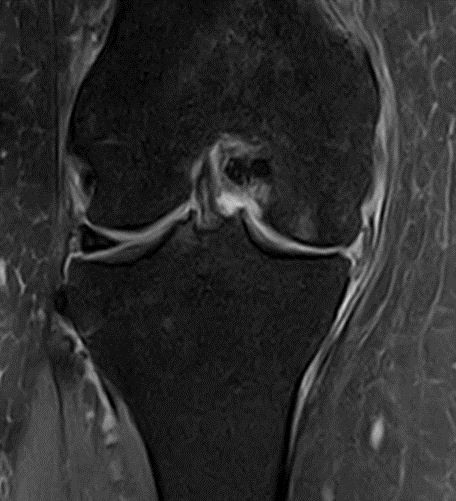

MRI scans illustrating the improvements regarding Group 2 are presented below, showing pre-treatment images with evident cartilage defects, pronounced bone marrow edema, and synovial inflammation, followed by post-treatment scans demonstrating improved joint structure, reduced edema, and decreased inflammation (Figures 12-29).

MRIs of Group 2

Figure 12: Female, 59 years, pre-intervention MRI.

Figure 13: Female of figure 12, 59 years, two-month follow-up MRI: MSC plus ChondroFiller® liquid.